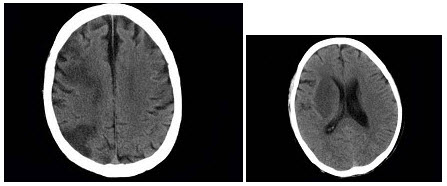

21、单项选择题

女,37岁,产后10天,出现剧烈头痛头昏伴神志不清2天,根据所提供图像,最可能的诊断是()

A.右侧蛛网膜下腔出血

B.右侧脑膜脑炎

C.右侧硬膜下血肿

D.右侧脑梗死

E.右侧静脉窦血栓形成